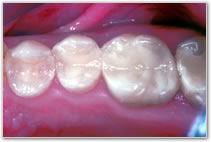

Kompositfüllung in Mehrschichttechnik

Die Komposit-Füllungen werden weiterhin mit einem modernen Adhäsivsystem (Mehrschicht-Ätz–Bonding-Klebetechnik) verarbeitet, was natürlich zeitaufwendig ist. Das Ergebnis ist den Aufwand wert, denn dafür bekommen Sie biokompatible, umweltfreundliche, langlebige, ästhetische und vor allem, eine von natürlichen Zähnen kaum zu unterscheidende, Kunststoff-Füllung.